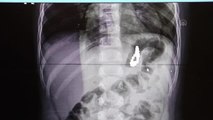

- Beylikdüzü’nde 9 yaşındaki çocuk oyuncak olarak satılan stres bilyeleri olarak da bilinen neodyum adlı güçlü mıknatıstan 42 adet yuttu. Kusma karın ağrısı şikayetiyle hastaneye getirilen çocuğun röntgen filmi çekilince gerçek ortaya çıktı. Ameliyata alınan çocuğun delinen bağırsağından mıknatıslar çıkarıldı. Beylikdüzü’nde 9 yaşındaki bir çocuk ailesinin haberi olmadan neodyum adı verilen stres bilyeleri olarak da bilinen 42 adet mıknatısı yuttu. Birkaç gün sonra şiddetli karın ağrısı ve kusma şikayeti ile hastaneye gelen çocuğun röntgeni çekildi. Röntgen filminde çocuğun midesinde boncuklar halinde yabancı bir cisim tespit edildi. Bağırsağını delen cismi fark eden Beykent Üniversitesi Çocuk Cerrahisi Uzmanı Prof. Dr. Ali Çay çocuğu ameliyata aldı. Yapılan ameliyatta çocuğun bağırsaklarından rengarenk şekilde 42 adet neodyum çıkarıldı. “Tesadüfen bu mıknatısları yuttuğunu biz radyografide gördük” Konuyla ilgili konuşan Prof. Dr. Çay, yutulan cisimlerin normalde sindirim sistemi ile çıkabileceğini ancak çoklu mıknatısların bağırsaklarda delinmeye neden olabileceğini ifade ederek, “Bizim hastamız yaklaşık 42 tane bu mıknatıstan yutmuş çeşitli hastanelere müracaat etmiş. Burada yapılan incelemelerde çekilen filmlerde tesadüfen bu mıknatısları yuttuğunu biz radyografide gördük hastamızı ameliyata aldık. İnce bağırsak uç kısmında delinme oluşturmuştu. Biz bu mıknatısları çıkardık” dedi.